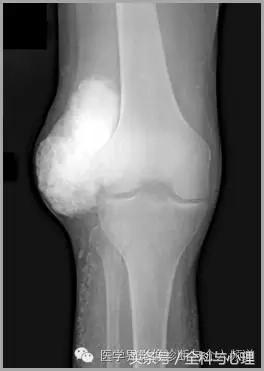

五、滑膜软骨瘤病

1°少见,病灶数量多,大小均匀,相邻关节正常。

2°多见,病灶数量少,大小不一,多伴有退行性骨关节病。

滑膜骨软骨瘤病 1°

滑膜骨软骨瘤病 2°

滑膜骨软骨瘤病